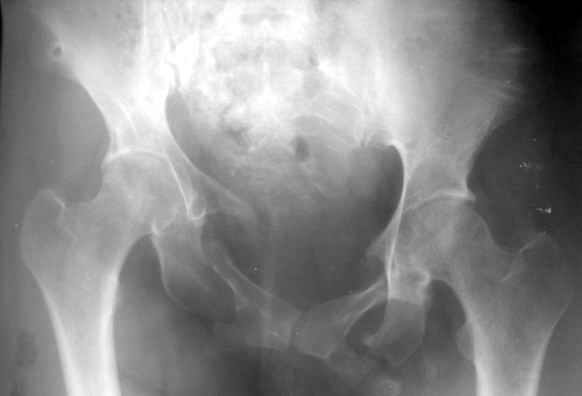

Застарелая деформация таза

Вопрос Уральскому Пельвиоцентру: через год после травмы, довольно симпатичная женщина, болей нет, только ходит призрамывая на правую ногу и сидит криво,

мышечная ассиметрия практически не выражена, хотя слабость справа есть. Легко компенсируется подкладкой стельки 1,5 см с выраженным клиническим эффектом. Посылаю снимки с вопросом - можно ли устранить деформацию в Вашем аппарате, если можно - то поподробнее. Снимки с разницей во времени почти 1 год. Жду ответа как соловей лета. ЛАФ.